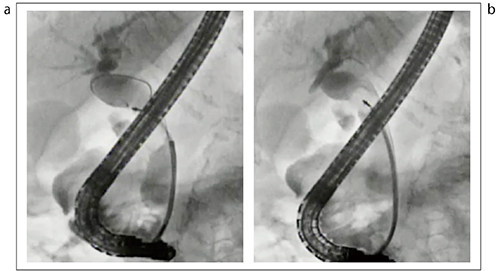

最後に、嵌頓結石について触れたい(図17)。嵌頓結石に対しては、ガイドワイヤ越しに行うことが有用である。ガイドワイヤがうまく奥まで入った場合には、必ず先端チップが細いバスケットあるいはバルーンを用いることで、安全に採石できる(図18)。また、POCSも有用なほか、当科では、レーザーあるいはEHLも実施することが多い。肝内胆管迷入嵌頓結石に対しては、パピロトーム(ナイフ)の刃を振って結石を肝外胆管まで移動させる方法もある(図19)。本症例は、そのままナイフで取り出したが、ナイフから結石を外し、バスケットで採石する方法もある。

図19 パピロトームによる肝内胆管嵌頓気味結石の除去

a:肝内胆管へ迷入した嵌頓結石への対応

b:パピロトームで結石を移動させる

c:乳頭から結石が排出された